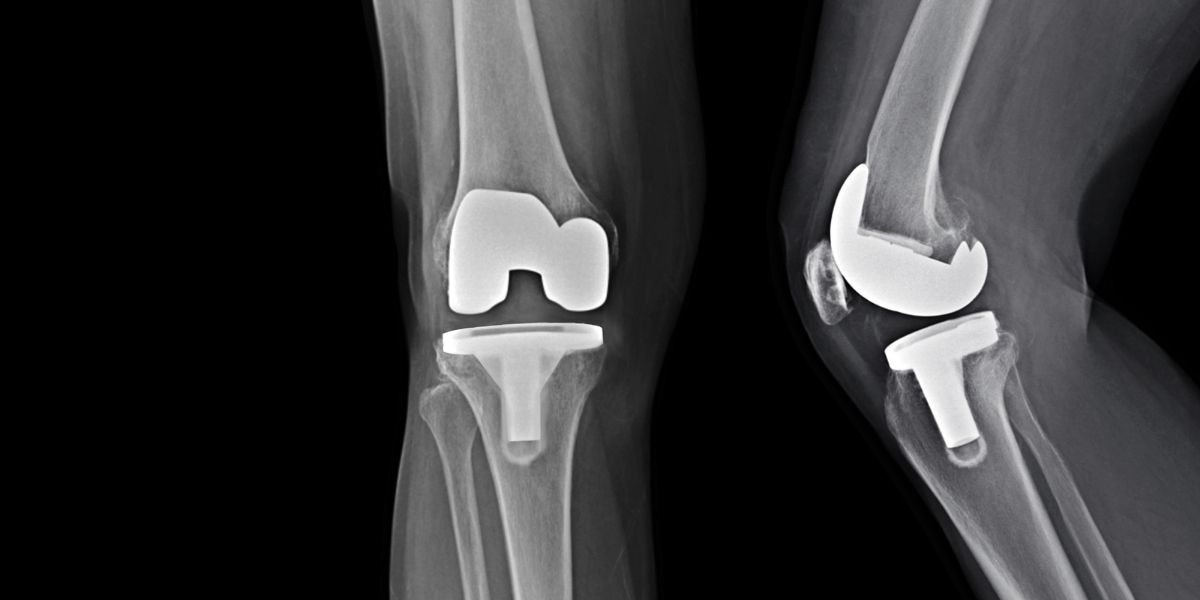

Quan el dolor no es pot controlar amb els analgèsics habituals, s’ha de fer una operació de reemplaçament total de genoll, també conegut com a PTG.

En la cirurgia, se substitueixen les superfícies articulars que pateixen la pèrdua de cartílag per un implant artificial fet de crom, cobalt o titani. Un cop s’extreu la part afectada, es col·loca l’implant metàl·lic i es fixa a l’os amb ciment.

A l’Hospital Universitari Vall d’Hebron fem fins a 500 intervencions de pròtesi de genoll a l’any.